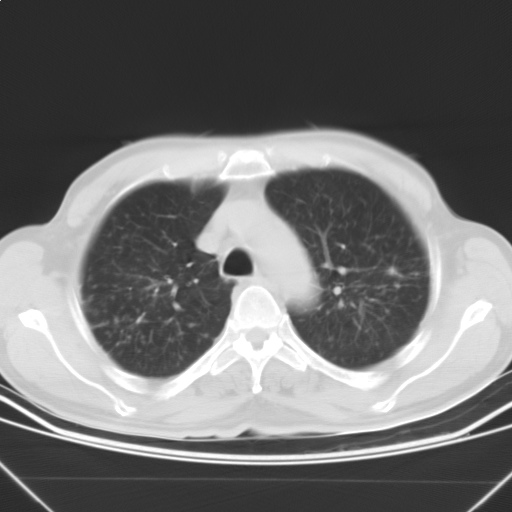

以下是引用随光逐影在2009-5-1 13:53:00的发言:[br]考虑为:1)两肺血行播散型肺结核;2)右肺下叶炎症感染。3)右侧胸膜增厚。